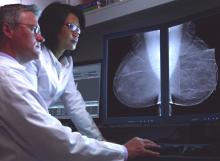

Patients who receive breast tomosynthesis for their annual breast cancer screening experienced fewer recalls, fewer diagnostic procedures, earlier detection and required less costly treatment than patients who utilized traditional, 2-D digital imaging alone, according to a new study by Truven Health Analytics.